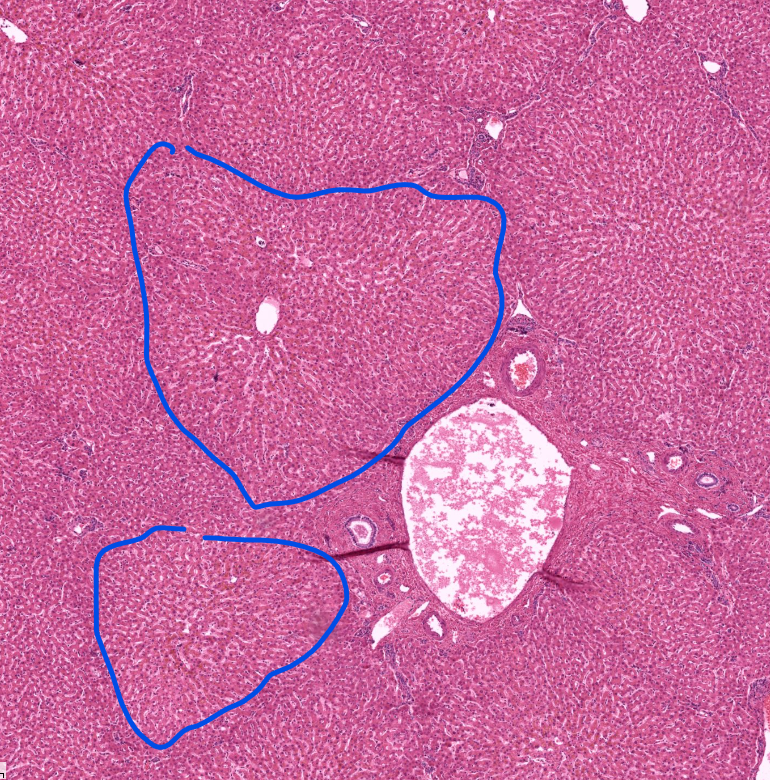

lobules of the liver

has arteries and veins and bile ducts at the “corners” aka portal triads

has a central vein for absorbed things to leave

liver

“sponge” bc it processes blood/nutrients/etc

notice geometric shapes and holes

portal triad of the liver

capillary/AV and bile duct

lobe (red) and lobule (blue) of the pancreas